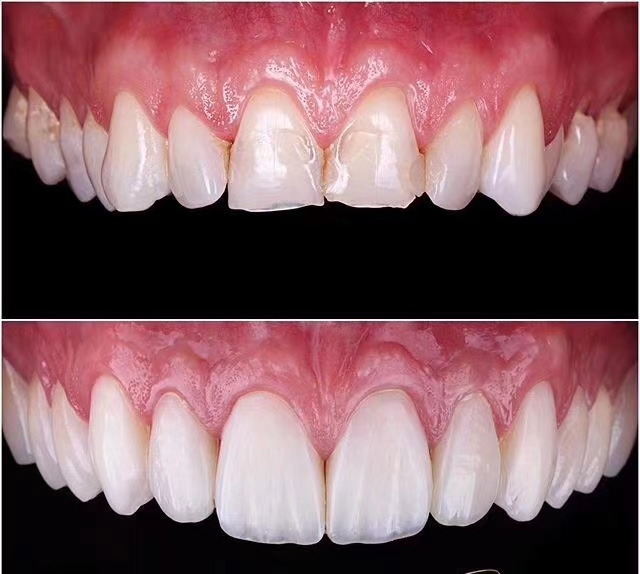

口腔科主要开展牙体牙髓治疗、牙周治疗、牙齿美容、齿槽外科治疗、义齿修复、种植牙、正畸治疗、儿童口腔治疗、口腔粘膜病的中西医结合治疗等多个业务项目。其中特色的种植牙业务及正畸治疗、牙体牙髓治疗项目,都是区内领先。